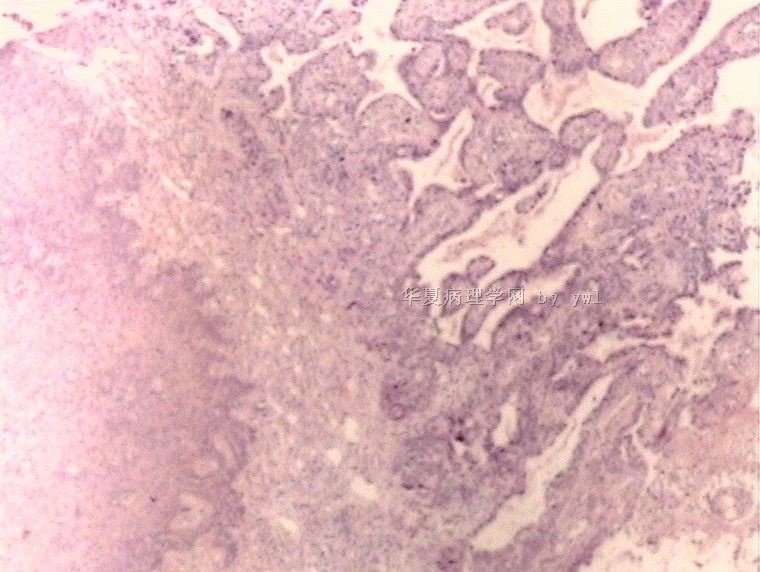

腺鳞癌?

姓    名: ××× 性别:   年龄:  39岁

标本名称:  宫颈活检

简要病史:  同房出血3次,tct HSIL

考虑:原位腺癌,小灶性区域有鳞状上皮向间质内浸润,考虑有鳞状细胞癌结构。

• 腺鳞癌?图4

图4